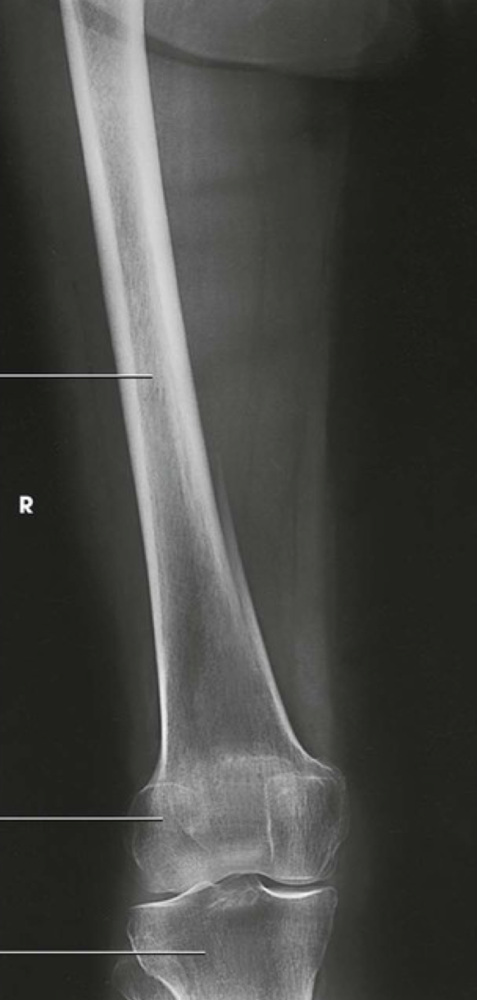

Question

Label the image

Image:

71af9f3b-876c-4373-99da-cdb4983a364f (image/png)

Answer

patella

femoral condyles

tibia

fibula

medial malleolus